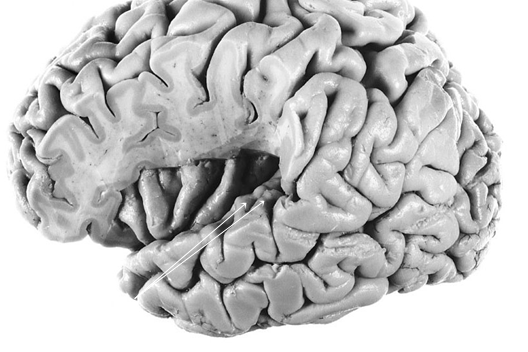

Hescl’s gyrus - primary auditory cortex

input - MGN via the posterior internal capsule

important for distuinguishing sound patterns

blue

hescl’s gyri